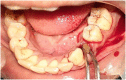

Purpose: This study aimed to evaluate the effectiveness of gelatamp on soft tissue healing, bleeding, and pain following mandibular posterior teeth extraction.

Methods: This study was designed as a split-mouth, prospective randomized double-blind controlled trial conducted in a single tertiary care center. Thirty-five subjects indicated for routine mandibular posterior teeth extraction were divided into two groups using the lottery technique: the experimental group (n = 30), which received gelatamp after extraction, and the control group (n = 30), which received no intervention. The primary outcomes included soft tissue healing(Landry, Turnbull, Howley index) and Pain(VAS score). The secondary outcomes assessed were bleeding(Maani et al. index) and swelling(Sauza and Consone assessment).

Result: The results showed a statistically significant difference in soft tissue healing on the third and seventh days in the experimental group (p ≤ 0.05) than in the control group. A significant difference in bleeding scores at 5 min, 30 min, and 2 h postoperatively in the study group (p ≤ 0.05) was noted. There was no significant difference between the groups for pain on the first, third or seventh day postoperatively (p ≤ 0.05). The swelling assessment also showed no significant changes (p = 0.831) for the study and the control group.

Conclusion: Based on the findings of this study, gelatamp can be effectively used to reduce postoperative sequelae such as bleeding with better soft tissue healing following extractions and surgical removal of tooth.